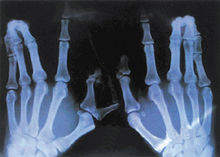

X線骨片可見輕重不等的佝僂病變化,活動期與恢復期病變同時存在,在股骨、脛骨最易查出。有骨齡落後膝外翻或內翻。乾骺端增寬,呈碎片狀,骨小梁粗大在脛骨近端、遠端以及股骨、橈骨、尺骨遠端乾骺端皆可出現杯口狀改變